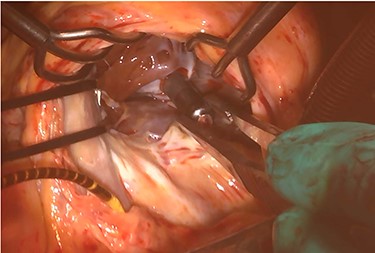

At his 1-year follow-up visit, the patient presented with shortness of breath on exertion and leg edema; thus, we decided to perform surgical correction. After median sternotomy, cardiopulmonary bypass was established with ascending aortic and bicaval venous cannulations. MyoPore (Greatbatch Medical, NY, USA) bipolar sutureless screw-in lead was attached to the left ventricle. A permanent PM was implanted, and left atrial appendage exclusion with AtriClip (AtriCure, OH, USA) was performed afterward. A right atriotomy was performed to facilitate exposure, wherein we found that the septal and posterior leaflets of the tricuspid valve were severely damaged (Fig. 3). Micra was placed over the right ventricular septum and was easily freed under direct vision (Fig. 4). After the leaflets were excised, an Epic (St Jude Medical, MN, USA) 33-mm bioprosthesis was implanted.

Intraoperative photograph; Micra was retrieved under direct vision.

Our search of the literature revealed no report of applying leadless PM as a bridge procedure. As previously described, leadless PM implantation could be a reasonable option after PM explantation for device infection. On the other hand, leadless PM, as with conventional PM, will need to be replaced due to generator limitations. In the presented case, we performed tricuspid valve repair and freed the leadless PM simultaneously. Of note, under direct vision, leadless PM could be retrieved safely. From this experience, we suggest that leadless PM as bridge procedure could be one option for patients who will possibility to need a more definitive surgical intervention in the future.